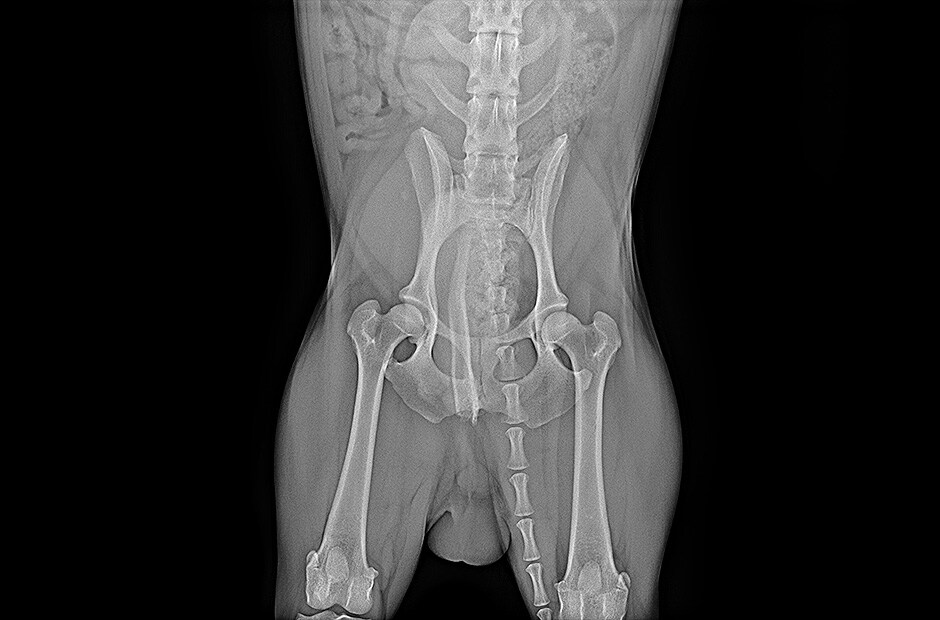

Amélioration de l'efficacité du travail

Disponibilité rapide des images

Disponibilité de l’image brute en 2 secondes avec une connexion filaire, ou 2,5 secondes avec une connexion sans fil

APPLICATION

Application

Radiographie Générale

TYPE TFT

Type TFT

a-Si

SCINTILLATEUR

Scintillateur

Csl

PIXEL PITCH

Pixel Pitch

140 µm

ZONE D’IMAGE

Nombre de Pixels

3072 x 3072 pixels

Zone Active TFT

430.08 x 430.08 mm

MTF

MTF @ 0.5lp/mm (Typ.)

89%

DQE

DQE @ 0.1lp/mm (Typ.)

72%